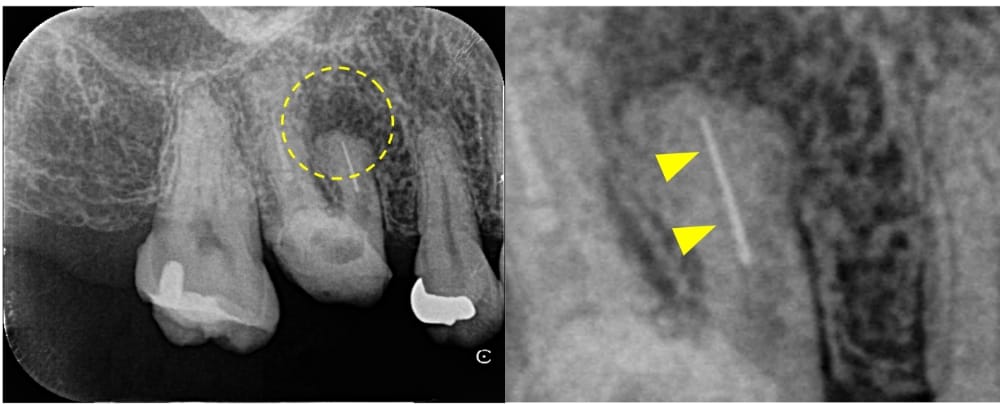

治療前にはっきりと写っていた根の先の材料ですが、術後12ヶ月では完全に消失しています。治療前には強く感じていた鈍い痛みもなくなり、良好な状態を維持しています。

CT画像による三次元的比較

CT画像上でも、根尖部の骨の回復と漏出していた材料の消失が認められます。